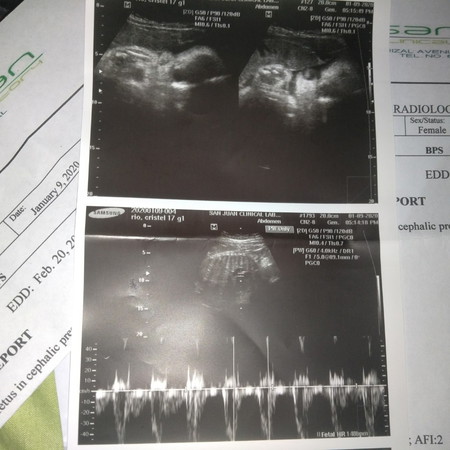

Hello po, bat po ganun sabi sakin dati nung nagpapa check up ako pati sa center ng brgy namin, sabi sakin february 20 daw po EDD ko. Tapos kanina nunt nagpa ultrasound ako sabi nung doktor february 8 daw po. Tapos akala ko po 34 weeks lang ako dito sa ultrasound ko 35 weeks naman ako ba magulo o talagang di ko lang maintindihan hahaha

Magbasa pahello po....same tayo sa oltrasound ko is coming to 35weeks ...may EDD is febrary 21 mas paniwalaan mo yong oltrasound kasi sa ontrasound makikita talaga..pero hindi na yan aabot sa expected date yong pag papanganak minsan ...kaso yong sa akin may problema kasi baliktad yong anak ko ..baka ma CS ako kasi baliktad ..